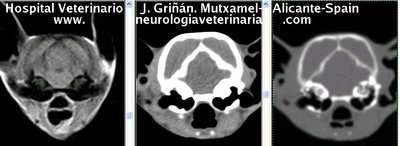

Se muestran cortes transversales de Resonancia Magnética (imagen a la izqda del lector), TC contrastado para tejidos blandos (imagen del centro) y TC contrastado para tejidos duros (imagen de la derecha del lector).

Nótese como la Resonancia supera al TC en el contraste de tejidos blandos (encéfalo y médula espinal) y en el de líquidos (ojo y líquido cefalorraquídeo), mientras que el TC supera a la resonancia en el contraste de tejidos duros (hueso) y aire (senos, cavidad nasal y bullas)

Cortes a nivel de los lóbulos occipitales del cerebro, parte craneal del cerebelo y puente. Nótense las bullas timpánicas. Nótense sendos oidos internos